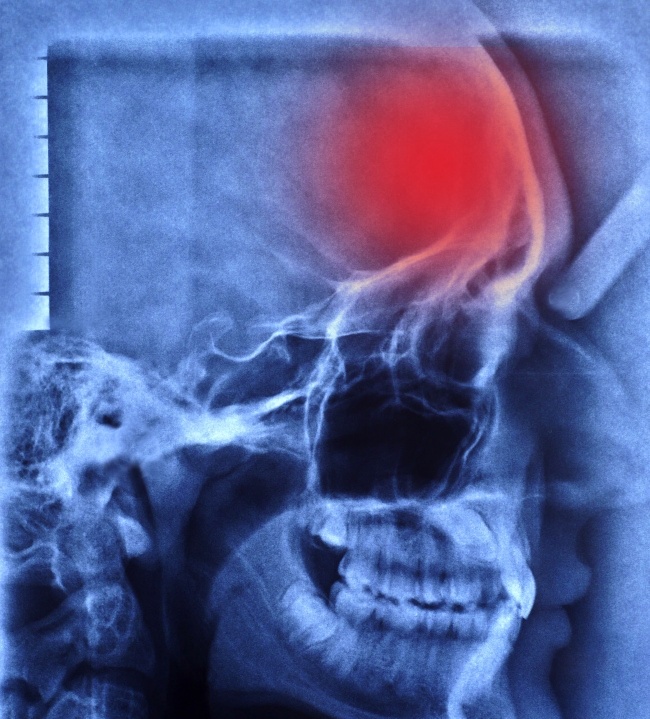

Лікарі виділяють 2 типу інсульту: геморагічний, або крововилив, і ішемічний — некроз (інфаркт) через закупорки судини.

Інфаркт мозку може з'являтися без чітких симптомів і проходити непомітно. Тому його часто називають «тихим інсультом».

Найбільш часта причина ішемічного інсульту — тромб, відкладення холестерину або спазм, який перекриває потік крові в ділянці мозку. Тканини навколо закупоренного судини набрякають, а простір в черепі обмежена. Підвищується внутрішньочерепний тиск, виникає один з частих супутників «тихого інсульту» — головний біль.